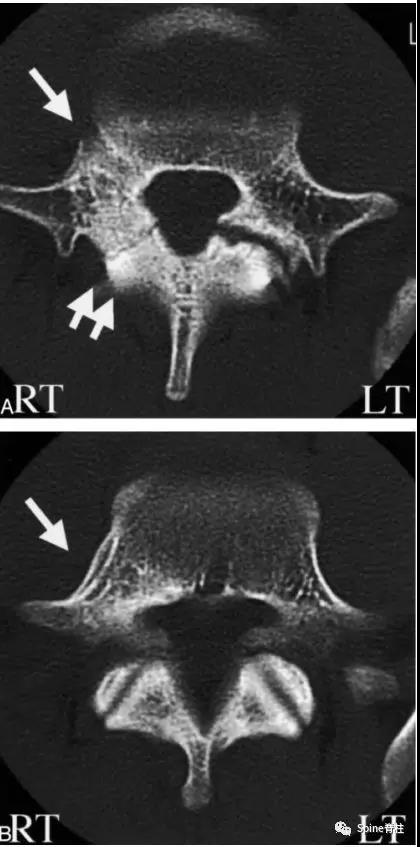

2003年发表在Am J Sports Med杂志(IF=6.20)上的病例报道,很好的阐述了峡部裂和椎弓根裂的变化。描述一个17岁的棒球运动员,运动后腰痛1月余,随访的辅助检查提示相同椎体水平出现的3个连续性应力性骨折:第一次为左侧峡部,第二次为右侧椎弓根,第三次为右侧峡部。

图:起始CT提示L5左侧峡部裂(双箭头),起始CT检查后2个月复查可见出现右侧椎弓根裂(单箭头),4个月复查可见椎弓根裂愈合(单箭头)

图:6个月复查可见右侧椎弓根裂已愈合(单箭头),但出现右侧峡部裂(双箭头)